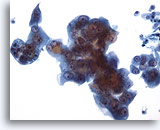

Peritoneal effusion: Metastatic carcinoma of the breast. Note malignant cells contrasting with benign histiocytes. Note large intracytoplasmic vacuoles with mucin droplets. 60X

Peritoneal effusion:

Metastatic carcinoma of the breast. Note malignant cells contrasting with benign histiocytes. Note large intracytoplasmic vacuoles with mucin droplets.

60X